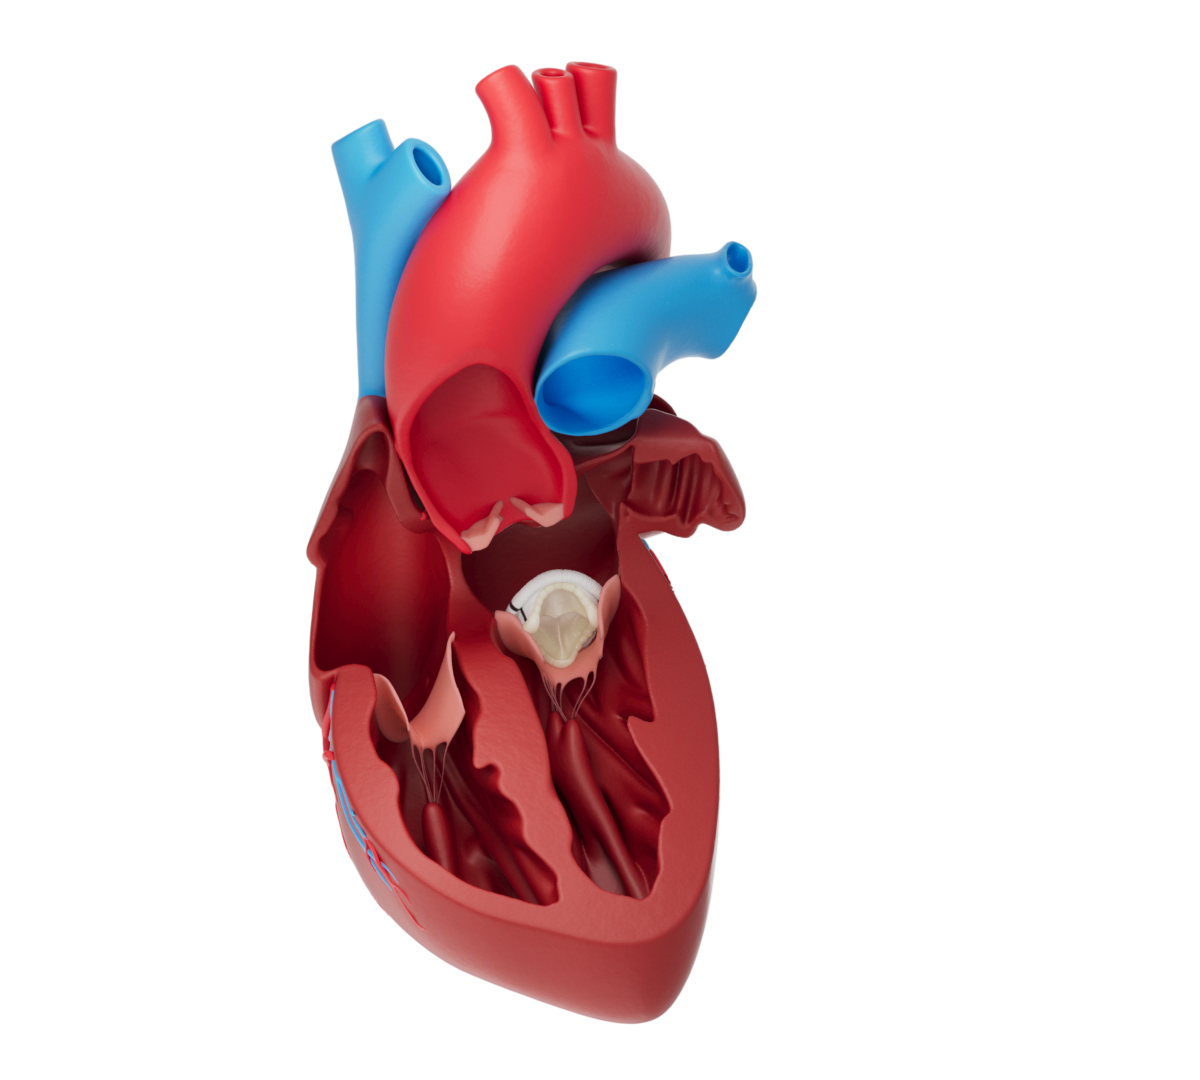

TISSUE HEART VALVE

Biological heart valve prostheses are made of animal tissue that has been carefully prepared for use in the human heart. Biological valve prostheses are divided into porcine valves, which consist of a porcine aortic valve, and pericardial valves, which consist of bovine or porcine pericardial tissue. The animal tissue is usually mounted on a scaffold (stent) for stabilisation. Your doctor will select the valve that best suits your needs and anatomical conditions.

The Epic Max valve is indicated for patients requiring replacement of a diseased, damaged, or malfunctioning native aortic valve. It may also be used as a replacement for a previously implanted aortic prosthetic heart valve.

Epic Max is an optimal solution for surgical aortic valve replacement and patient lifetime management. The larger redesigned internal orifice helps to alleviate the burden on the heart and reduce the load on the left ventricle. Having an index valve with a larger internal orifice area, low stent posts, and non-curtaining leaflets also has a positive effect on future valve-in-valve procedures. With the rise of transcatheter aortic valve replacement (TAVR) or transcatheter aortic valve implantation (TAVI) procedures, the Epic Max valve is a promising option for patients today, tomorrow, and the road ahead.

The Platform for Possibility

The Epic Platform has been proven over time and defined by strong hemodynamics, intuitive implantability, a future-forward design, and more. The platform boasts the low ventricular protrusion in all valve sizes, a flexible polymer stent, individually selected porcine leaflets to ensure optimal coaptation, and a flexible sewing cuff designed to minimize both in-implant suture drag and post-implant paravalvular leak.